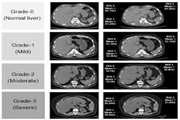

بررسی دقت تشخیصی سی تی اسکن با کنتراست در تشخیص و grading کبد چرب در مقایسه با نمونه های پاتولوژی بیمارانی که طی سال های96 تا 99 در بیمارستان امام خمینی تحت عمل جراحی هپاتکتومی قرار گرفته اند 1404/01/17 - 10:43